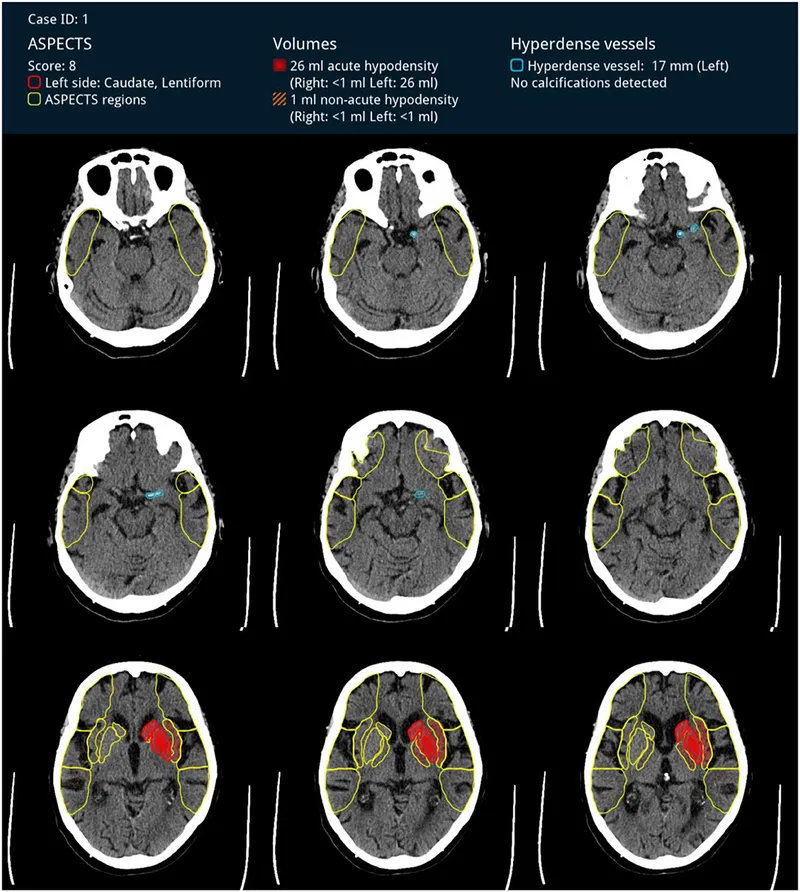

ASPECTS (Alberta Stroke Program Early CT Score): Quantifies early MCA ischemic changes on NCCT. Score 0-10 (10=normal). Lower score = worse outcome.

- 📌 Areas: Caudate, Lentiform nucleus, Internal capsule, Insular cortex, plus M1-M6 (MCA cortical regions).

Non-Contrast CT (NCCT): First-line to exclude hemorrhage.

- Early ischemic signs (<6 hrs): Hyperdense MCA sign (clot), loss of grey-white differentiation, insular ribbon sign (obscuration), sulcal effacement.